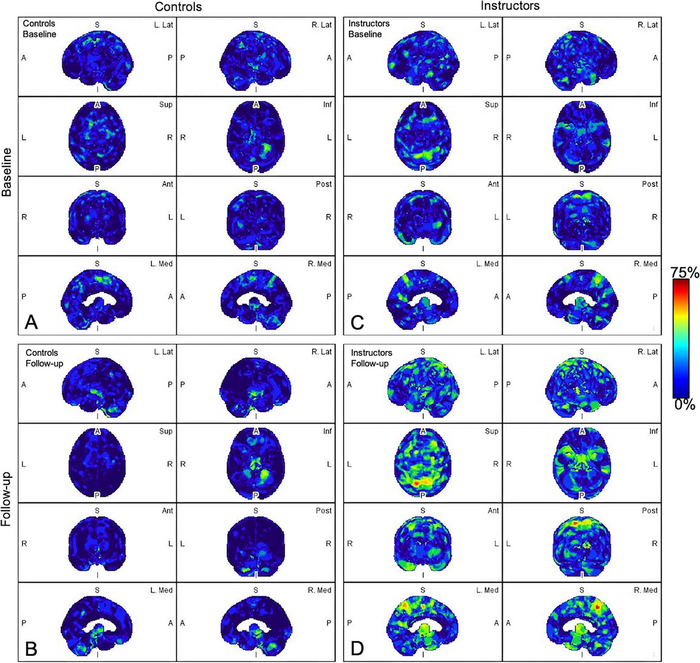

All participants underwent a PET scan of the head to evaluate and quantify amyloid changes. Analysis software was used to segment six brain regions that are usually associated with Alzheimer’s disease and TBI.

Abnormal amyloid accumulation was seen in six of the nine participants who were exposed to explosions. Three of the participants had one region of the brain with increased amyloid accumulation, two participants had two regions, and one participant had three regions with abnormal accumulation.

None of the healthy control participants showed any abnormal amyloid accumulation.